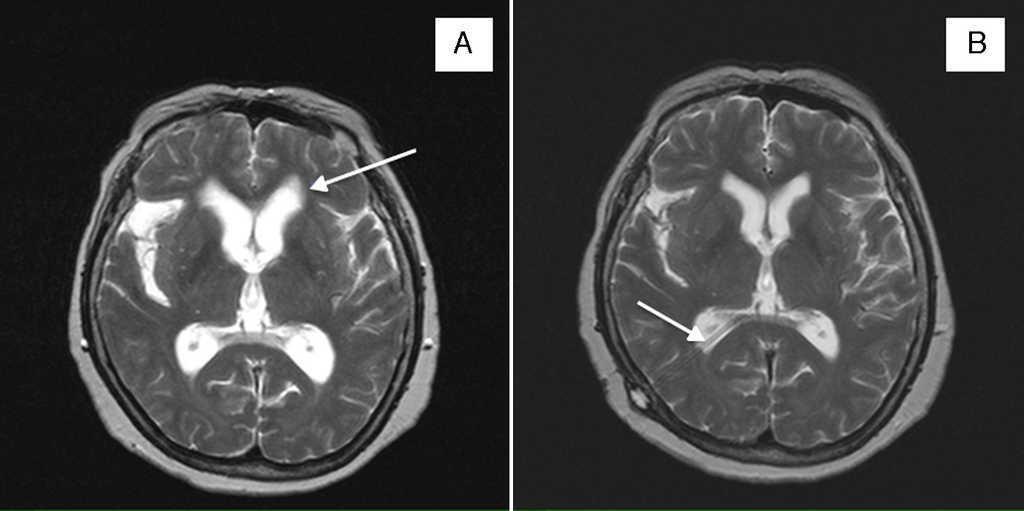

Quiste De La Cisura Coroidea Tratamiento, , , , , , , 0, PPT - PSEUDOLESIONES EN NEUROIMAGEN PowerPoint Presentation, free, www.slideserve.com, 1024 x 768, jpeg, WebThey are usually small and range around about 1-2 cm in diameter. Occasionally, larger cysts may be seen. The cysts are usually round on axial and coronal images, with a characteristic spindle or ovoid shape paralleling the long axis of the. WebQuiste de la cisura coroidea: Se trata de lesiones nodulares bien definidas con localización típica en la cisura coroidea (entre la fimbria del hipocampo y el diencéfalo). Webquiste_de_la_cisura_coroidea. Quiste ovoideo con bordes finos y que por su morfología y localización parecen originarse en la cisura coroidea (espacio entre la fimbria del. WebMe dieron el resultado de una resonancia magnética craneal, todo salió normal a excepción de dos quistes: Pequeño quiste de la cisura coroidea izquierda de 5,8 mm y quiste., 20, quiste-de-la-cisura-coroidea-tratamiento, Novedades y Muebles WebThey are usually small and range around about 1-2 cm in diameter. Occasionally, larger cysts may be seen. The cysts are usually round on axial and coronal images, with a characteristic spindle or ovoid shape paralleling the long axis of the. WebQuiste de la cisura coroidea: Se trata de lesiones nodulares bien definidas con localización típica en la cisura coroidea (entre la fimbria del hipocampo y el diencéfalo). Webquiste_de_la_cisura_coroidea. Quiste ovoideo con bordes finos y que por su morfología y localización parecen originarse en la cisura coroidea (espacio entre la fimbria del. WebMe dieron el resultado de una resonancia magnética craneal, todo salió normal a excepción de dos quistes: Pequeño quiste de la cisura coroidea izquierda de 5,8 mm y quiste.

WebQuiste Fisura Coroidea. Lo primero es definir lo que es la fisura coroidea. Corresponde a un espacio de LCR entre la fimbria del hipocampo y el diencéfalo. Generalmente. WebCisura coroidea. Espacio entre la fimbriadel hipocampoy el diencéfalo. ver quiste de la cisura coroidea. cisura_coroidea.txt. Última modificación: 2019/09/26. Web-Grupo tratamiento: Pacientes con glaucoma tratados durante más de 1 año con al menos 1 antiglaucomatosos por vía tópica. -Grupo control: Pacientes que no reciben ningún. WebQuiste cisura coroidea como hallazgo en TAC solicitado por cefalea. Descargar caso en PDF. Enviar caso a un amigo. Hombre | 42 años. Diagnóstico final: Quiste Cisura. WebAunque mejoran sin tratamiento, es posible eliminarlos con mayor rapidez a través de una inyección de corticoide local o cirugía. Los quistes epidermoides. WebEn caso de que surjan síntomas, se puede intentar controlarlos con medicamentos analgésicos, anticonvulsivos o para el mareo y las náuseas, prescritos. Web6) Quiste de la cisura (fisura) coroidea. La fisura coroidea es una estrecha hendidura de LCR entre el diencéfalo y la fimbria del hipocampo, conteniendo plexos coroideos.. WebA continuación, puedes ver ver un listado de opiniones sobre quiste cisura coroidea y opinar sobre este tema. Aquí podrás encontrar opiniones relacionadas con quiste cisura.

WebQuiste de la cisura (fisura) coroidea. La fisura coroidea es una estrecha hendidura de LCR entre el diencéfalo y la fimbria del hipocampo, conteniendo plexos coroideos. 19,20,21. WebLa mayoria de los quistes son extirpables. Debe consultarlo con un neurocirujano. Para determinar si el quiste es causal de una convulsion deben realizarle EEG y determinar. WebTratamiento: En los casos sintomáticos o lesiones que han alcanzado cierto tamaño, el tratamiento de elección será la resección quirúrgica. Esta puede realizarse por medio de.

Web6) Quiste de la cisura (fisura) coroidea. La fisura coroidea es una estrecha hendidura de LCR entre el diencéfalo y la fimbria del hipocampo, conteniendo plexos coroideos.. WebA continuación, puedes ver ver un listado de opiniones sobre quiste cisura coroidea y opinar sobre este tema. Aquí podrás encontrar opiniones relacionadas con quiste cisura. Web• Quiste de los plexos coroideos • Quiste de la cisura coroidea • Quistes aracnoideos (2%) • Quistes de la pineal (2 – 4%) • Lipoma del filum terminale • Quistes perineurales de.